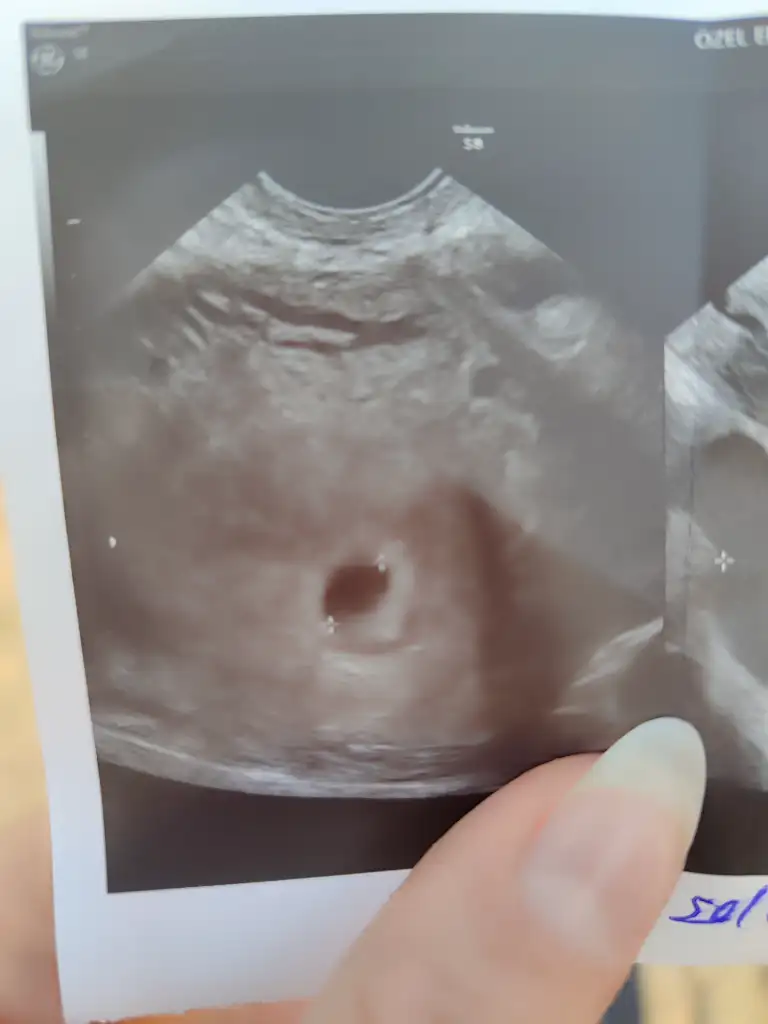

Kızlar kesemizi gördük bugün cok sukur 4+6 çıktı tam yumurtlama zamanıma uygun reglim uzun olduğu ıcın doktor sat 5 ekim olarak söyle dedi muayene gittiğin zaman haftaya çarşamba tekrar gidicem inşallah kalp atışı duyulur 6+1 oluyor emin değilim ama en azından bebişide görsem olur

• IMG_20251110_150305.webp

kaç mm ölçüldü keseniz vajinal mi bakıldı